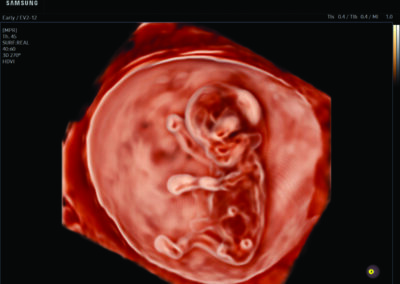

Comprehensive, advanced and expert MFM care for high-risk pregnancies

- Fetal anomalies